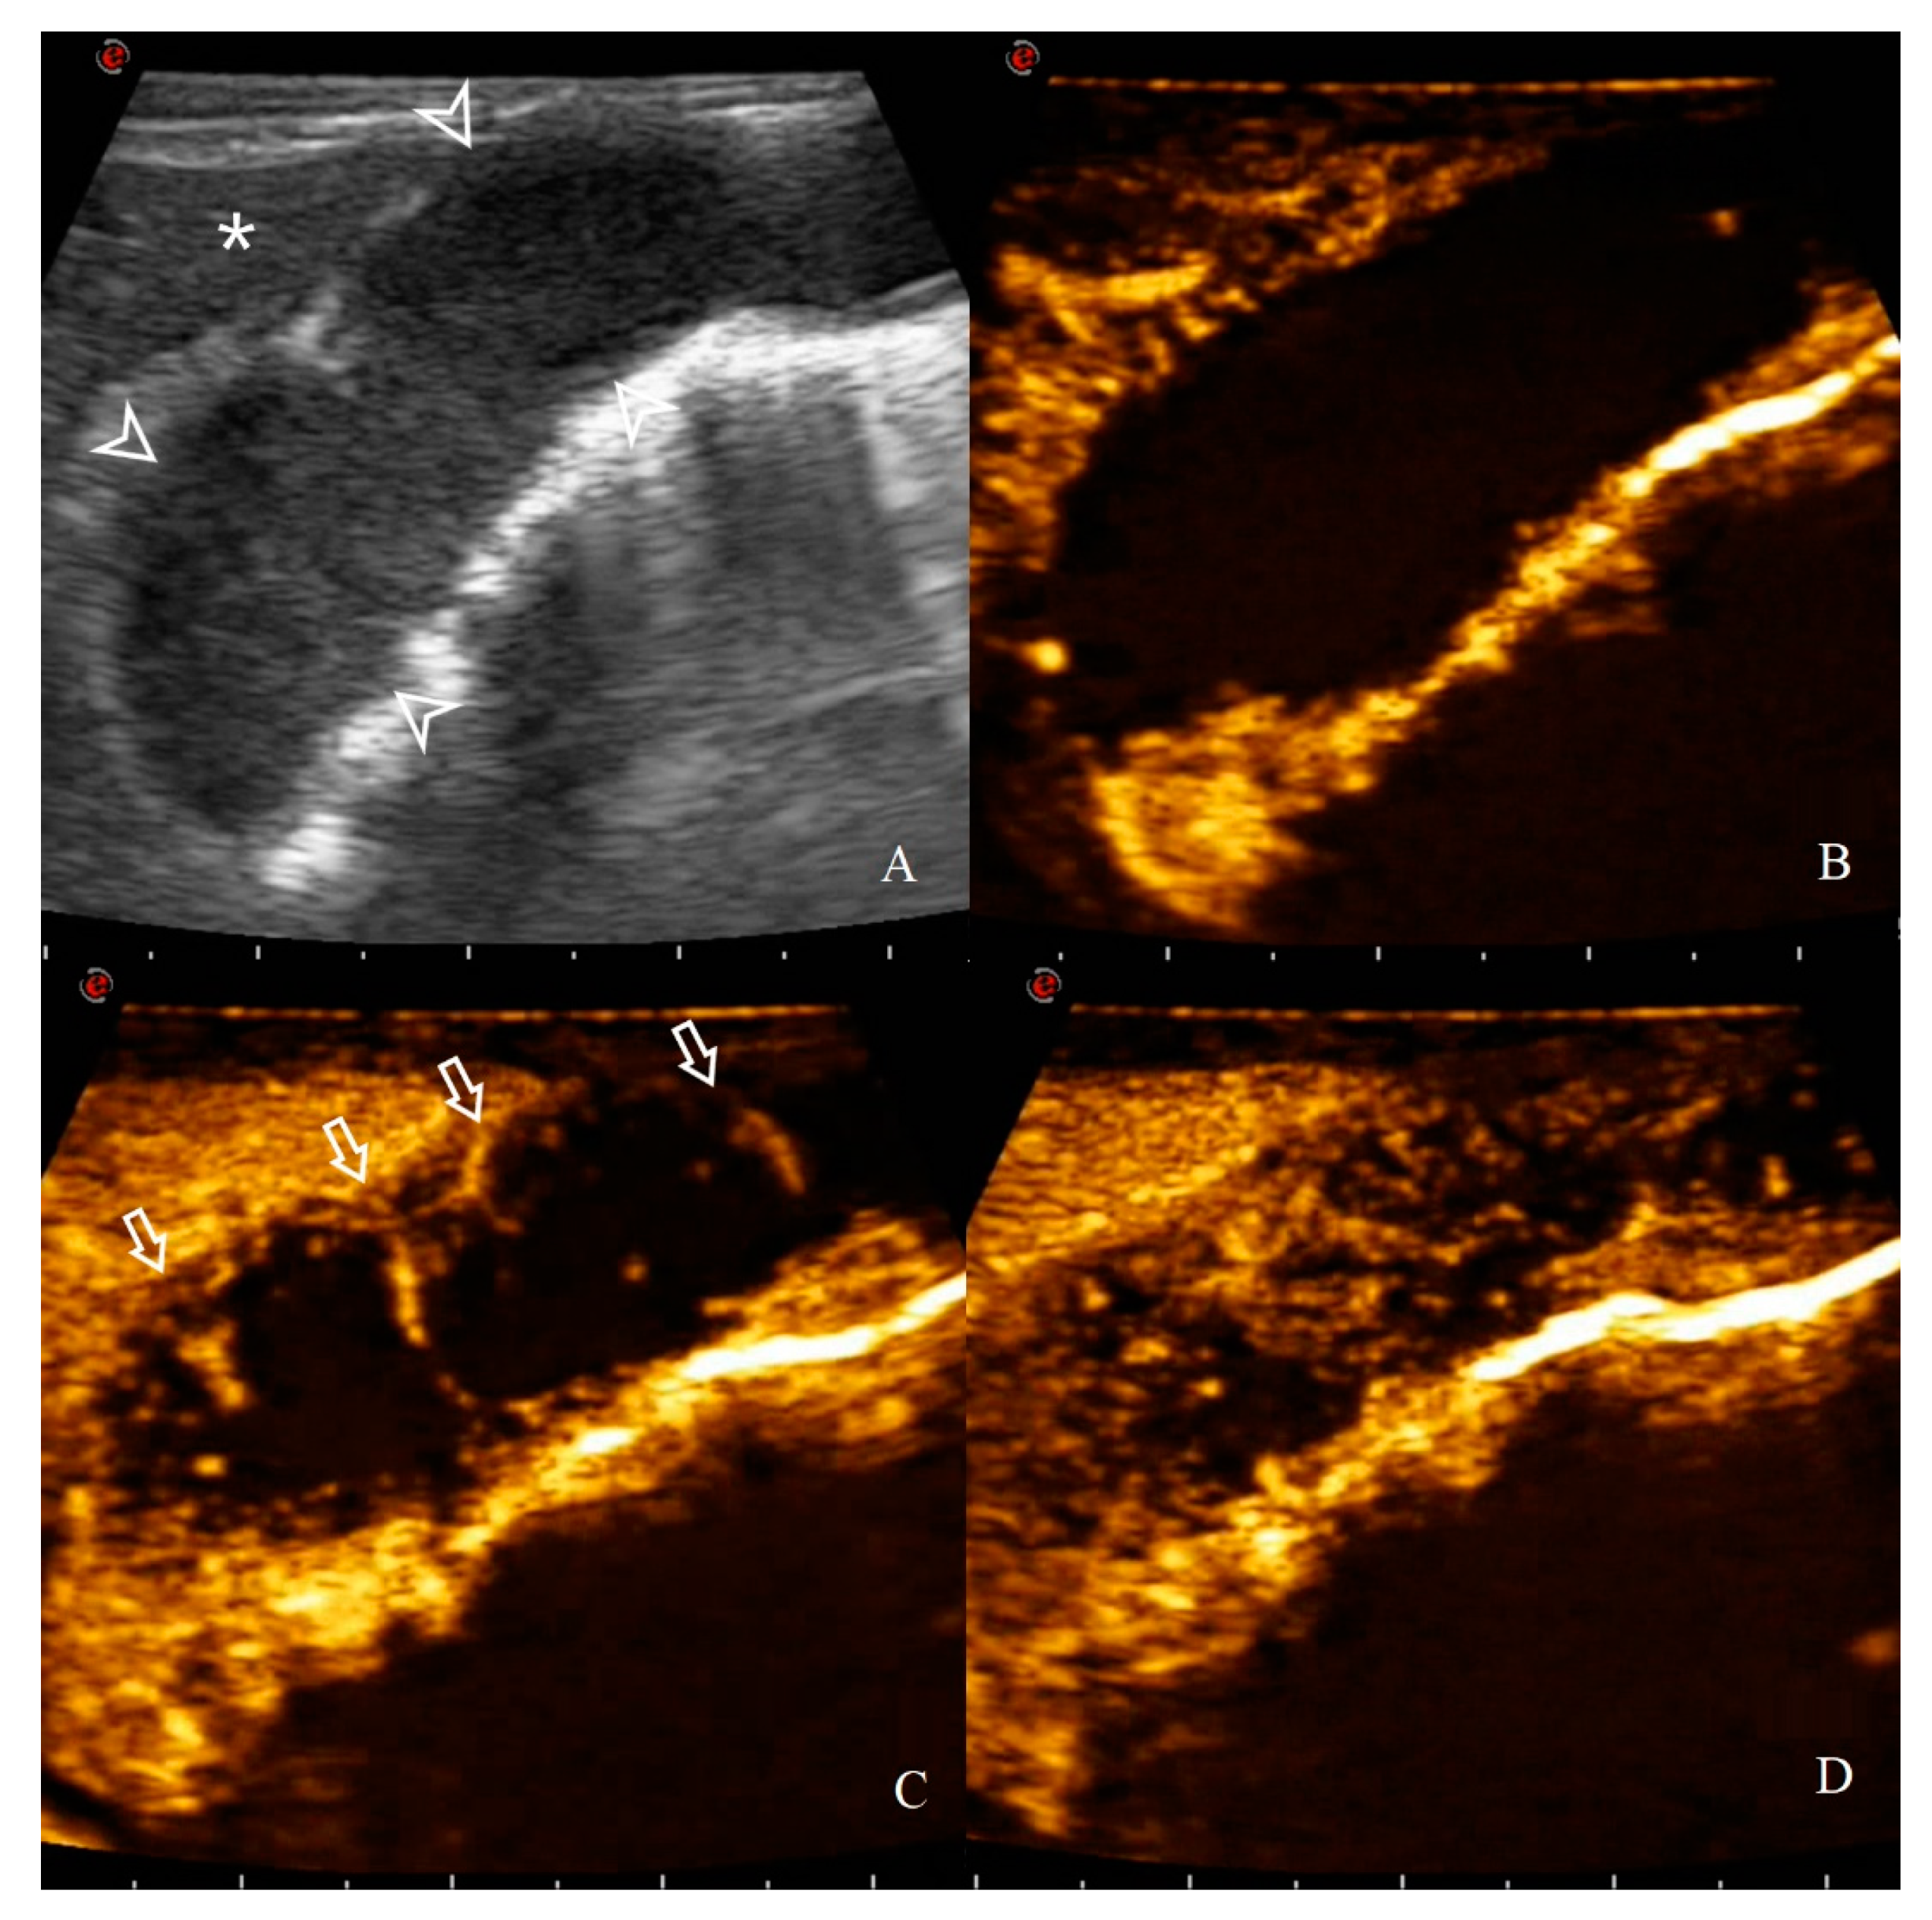

CEUS qualitative assessments were evaluated only for the HGAL since all the cats with a gastric wall thickening ≥6 mm belong to this group. The enhancement patterns of the 10 HGAL on CEUS are reported in Table 4. HGAL showed a variable enhancement degree if compared to the adjacent liver parenchyma (5/10 hyper and 5/10 hypo/iso enhancement). Furthermore, lymphomas of this group were more likely to have a homogeneous enhancement (7/10) and the presence of comb teeth-like vessels (7/10) (Figure 11).

Figure 11. CEUS enhancement pattern in a 7-year-old cat with gastric HGAL: (A) before contrast medium (CM) injection (0 s), the gastric mass (14.8 mm between arrowheads) and the adjacent liver parenchyma (asterisk) are visualized; (B) after CM injection (8 s), uptake occurs first in the liver and the gastric mass is classified as hypo-enhancing; (C) when CM arrives at the lesion site (14 s), comb teeth-like vessels are present (arrows); (D) at peak enhancement time (18 s), arterial branching is not visible anymore and enhancement homogeneity is classified as heterogeneous.